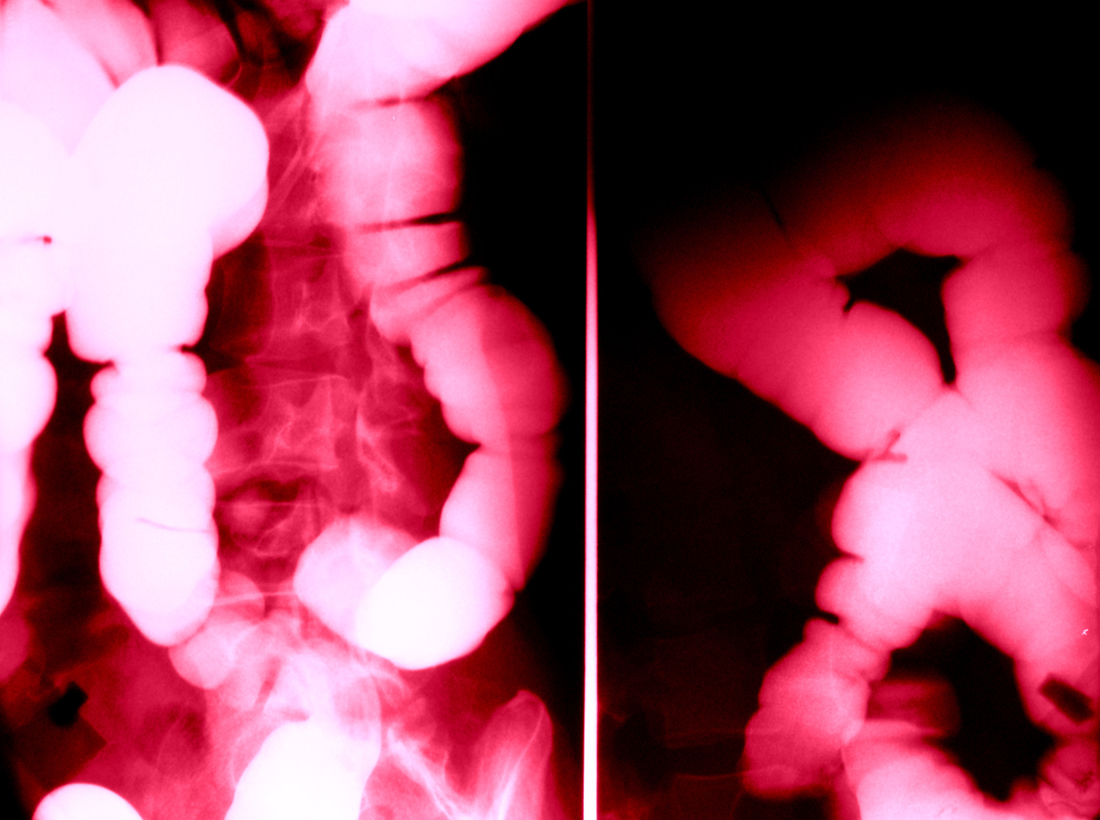

Intestine Xray (X-ray) photo